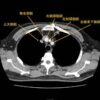

・咳,痰,呼吸困難

・上大静脈症候群,不整脈,心タンポナーデ

・胸痛,背部痛,Horner症候群,嗄声

・(胸部X線,CTにて)縦隔内に腫瘤影

・上記のような症状がある場合は大抵が悪性【治療】